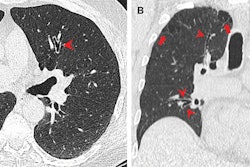

Daly also described a very ill patient who arrived in the emergency room with what appeared to be severe pneumonia on chest radiography.

"The patient had been sick at home taking antibiotics for at least a week," Daly said. "He had a CT scan, which found a horrible pneumonia that had turned into a lung abscess because the patient's bronchus intermedius was obstructed by a vial of crack cocaine. He'd aspirated [rather than swallowing] it when running from police two weeks earlier. This patient had to have the entire lung lobe removed."